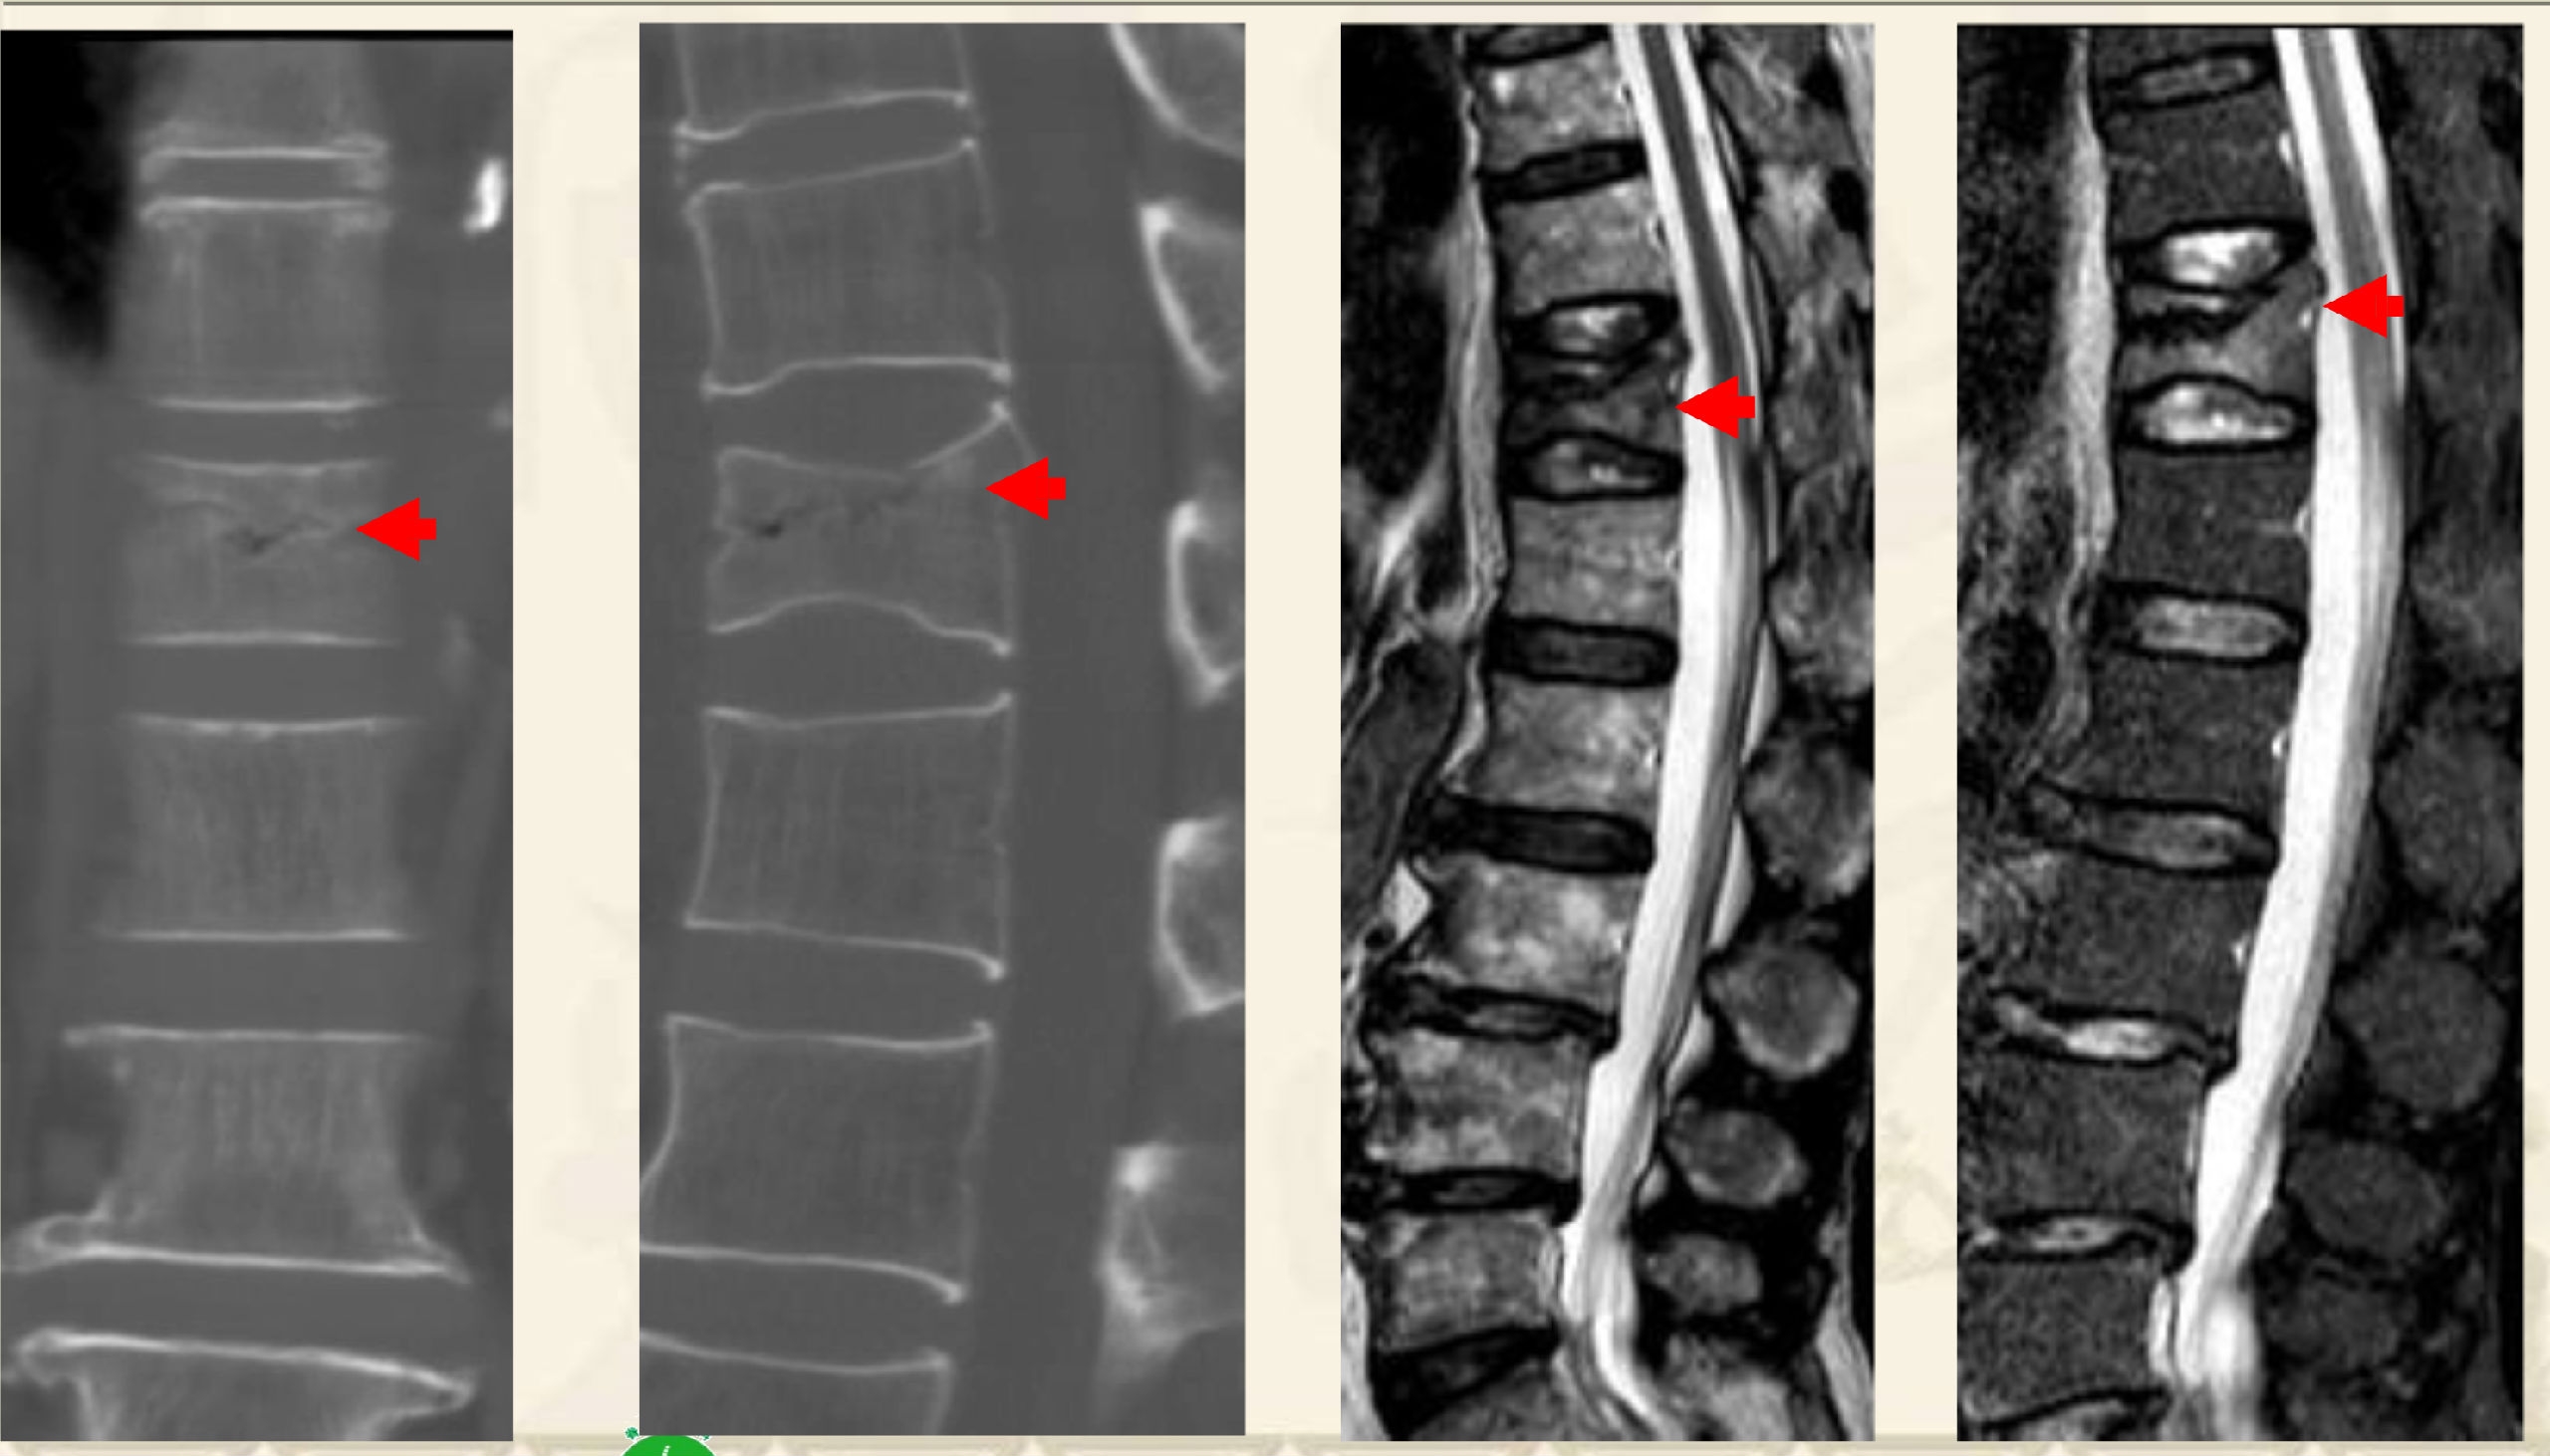

压缩后嵌插型骨折线,CT:高密度带、MRI低信号带。

压缩后自动复位裂隙型,CT:裂隙,MRI:低信号区(气体)

压缩后自动复位裂隙型

CT:裂隙,MRI:高信号区(液体)